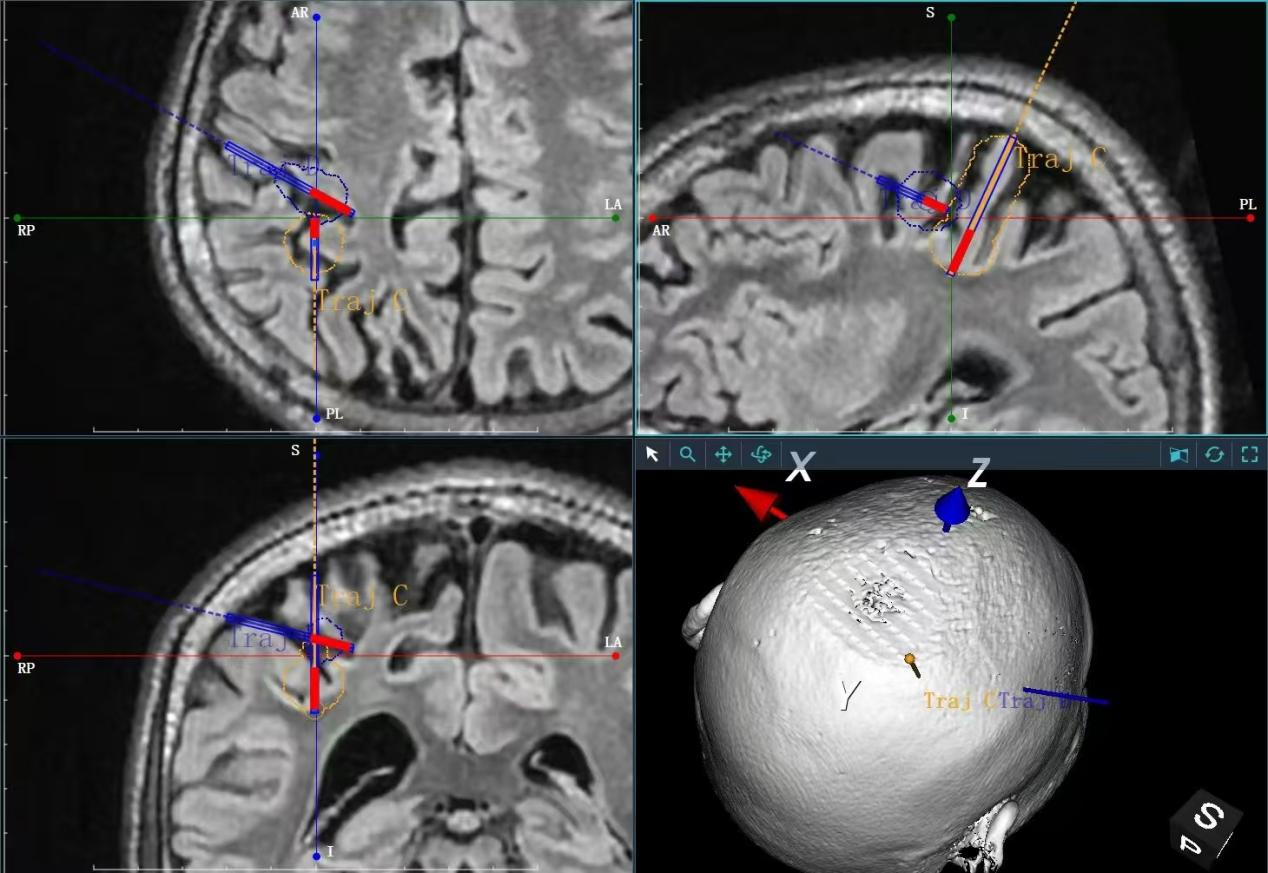

激光治疗过程图示

在消融阶段,系统以41℃~45℃的温度对病灶进行可控加热。术中磁共振连续扫描,实时生成三维温度分布图并投射于手术屏幕,使医生能够同步观察消融范围,确保其严格限定在病灶边界内,不损伤周边正常神经纤维。